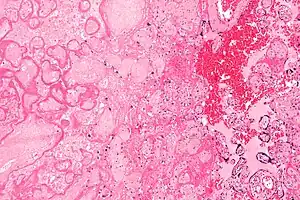

| Micrograph of a placental infarct (left of image), a cause of intrauterine hypoxia. H&E stain. | |

Intrauterine hypoxia (also known as fetal hypoxia) occurs when the fetus is deprived of an adequate supply of oxygen. It may be due to a variety of reasons such as prolapse or occlusion of the umbilical cord, placental infarction and maternal smoking. Intrauterine growth restriction may cause or be the result of hypoxia. Intrauterine hypoxia can cause cellular damage that occurs within the central nervous system (the brain and spinal cord). This results in an increased mortality rate, including an increased risk of sudden infant death syndrome (SIDS). Oxygen deprivation in the fetus and neonate have been implicated as either a primary or as a contributing risk factor in numerous neurological and neuropsychiatric disorders such as epilepsy, attention deficit hyperactivity disorder, eating disorders and cerebral palsy.[1][2][3][4][5][6]